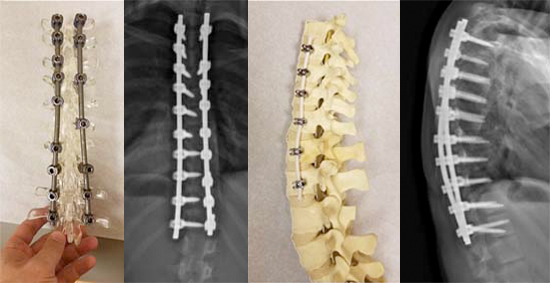

For patients with severe progressive variants of scoliosis, posterior spinal fusion offers the possibility of correction but prevents further growth of the fused segment of spine as well as restricting motion. Anterior vertebral body tethering provides an alternative that may mitigate these risks in younger patients with curves less than 65 degrees and significant growth remaining. In anterior vertebral tethering, screws are placed in the front of the spine and attached to each other with a flexible, polyethyleneterephthalate cable on the convexity of the curve. Compared to fusion techniques, this surgery corrects the underlying pathology while allowing continued spinal growth and preserving motion.

Fusion hardware and postop X-ray and VTB hardware and postop X-ray